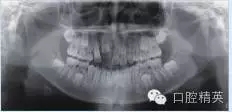

輔助檢查:全頜曲面斷層片顯示左側(cè)下頜骨體部可見(jiàn)類圓形高密度影,周圍可見(jiàn)低密度影環(huán)繞(圖1a);CT顯示:左側(cè)下頜骨體部呈膨脹性骨質(zhì)改變,局部骨皮質(zhì)變薄,內(nèi)伴高密度骨質(zhì)硬化影,邊界尚清晰,周圍軟組織腫脹(圖1b)。

圖1 a:全頜曲面斷層片;b:CT影像

入院檢查:混合牙列,11-12牙區(qū)見(jiàn)唇腭側(cè)牙槽骨膨隆,腭側(cè)較明顯,表面黏膜顏色正常,觸診質(zhì)地硬,無(wú)壓痛感。輔助檢查:全頜曲面斷層片及CT顯示11牙胚存在,其冠方牙槽骨內(nèi)高密度團(tuán)塊影,周圍可見(jiàn)低密度帶,與周圍骨組織分界清(圖2a、b)。

圖2 a:全頜曲面斷層片;b:CT影像

本文報(bào)告的病例1臨床表現(xiàn)為長(zhǎng)時(shí)間36、37未萌出,因38牙周腫痛,行牙拔除術(shù)后出現(xiàn)拔牙創(chuàng)長(zhǎng)期不愈,腫瘤周圍軟組織慢性感染灶穿通頰部皮膚形成皮瘺并伴有張口受限。X線表現(xiàn)為36、37完全骨埋藏,周圍見(jiàn)骨密度不均勻及低密度帶,伴有周圍頜骨膨脹畸形。病例2臨床表現(xiàn)為乳切牙脫落后恒切牙未萌出,X線表現(xiàn)為牙槽骨內(nèi)類圓形高密度影腫物,周圍可見(jiàn)低密度帶形成,頜骨向唇腭向膨隆,唇側(cè)骨皮質(zhì)壓迫吸收。